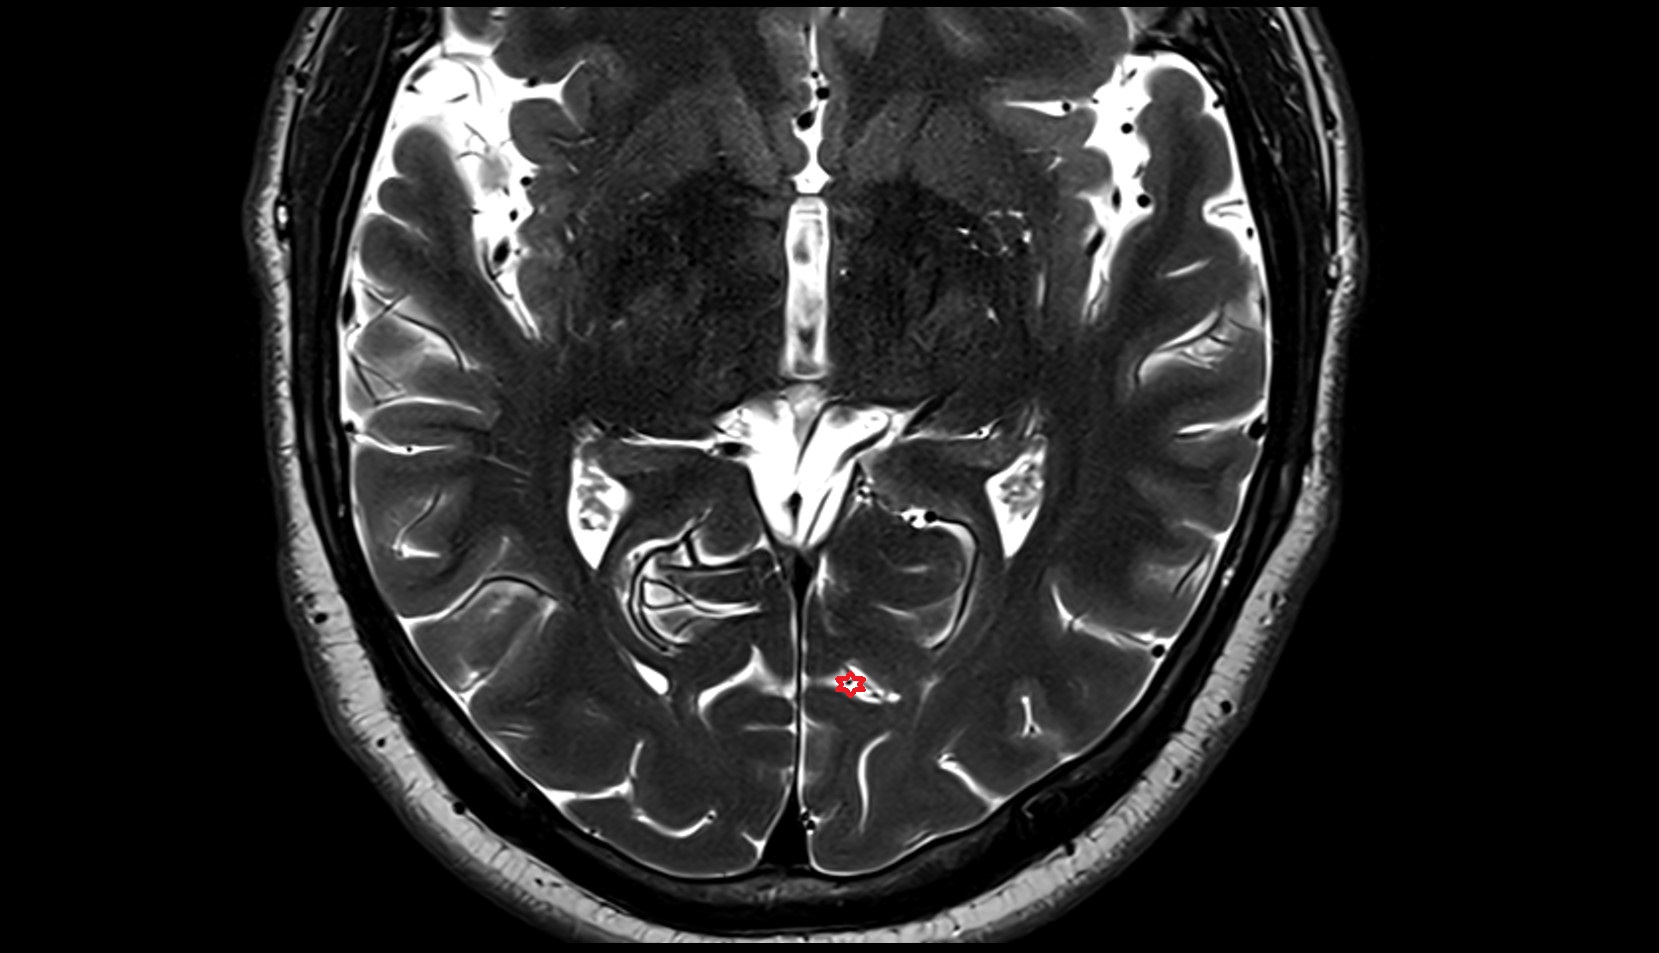

- Cerebral aqueduct

- Superior opening of cerebral aqueduct